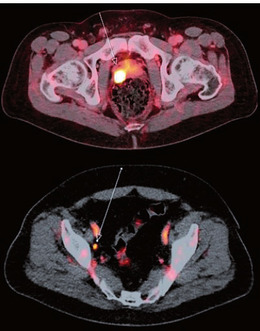

Bei high-risk Karzinomen ist ein Staging mittels einer prostataspezifischen Membranantigen-gestützten Positronen-Emissions-Tomographie sowie Computertomographie (PSMA-PET-CT) empfohlen.4 Im Vergleich zum konventionellen Staging kann durch ein PSMA-PET-CT eine höhere Genauigkeit in der Detektion von Metastasen erzielt werden. Aufgrund fehlender prospektiver Studiendaten bezüglich der Therapiesequenz nach erfolgtem, präziserem Staging mittels PSMA-PET-CT ist eine regelrechte Anwendung für alle Risikoklassen kritisch zu diskutieren. Aktuell ist ein PSMA-PET-CT als Primärstaging keine Regelleistung der gesetzlichen Krankenkassen.

Abb. 2 PSMA-PET-CTs mit vermehrter PSMA-Expression in der Prostata (oben) und einem suspekten Lymphknoten (unten)©Urologische Klinik und Poliklinik, Klinikum rechts der Isar, F. Kirchhoff